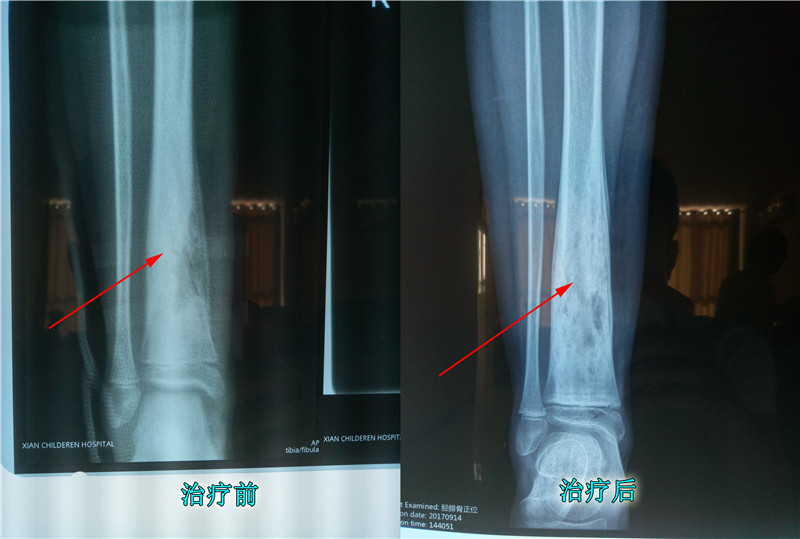

还有的患者是因为通过治疗,没有将坏死骨组织恢复。在治疗骨髓炎时,骨组织的恢复比外在的伤口恢复要难,也不容易清理干净。如果骨组织恢复不良,里面的细菌清理不干净,这就相当于你斩草不除根,这要有春风,就会再生。这种患者一般在治疗康复几年后,会再次复发骨髓炎。